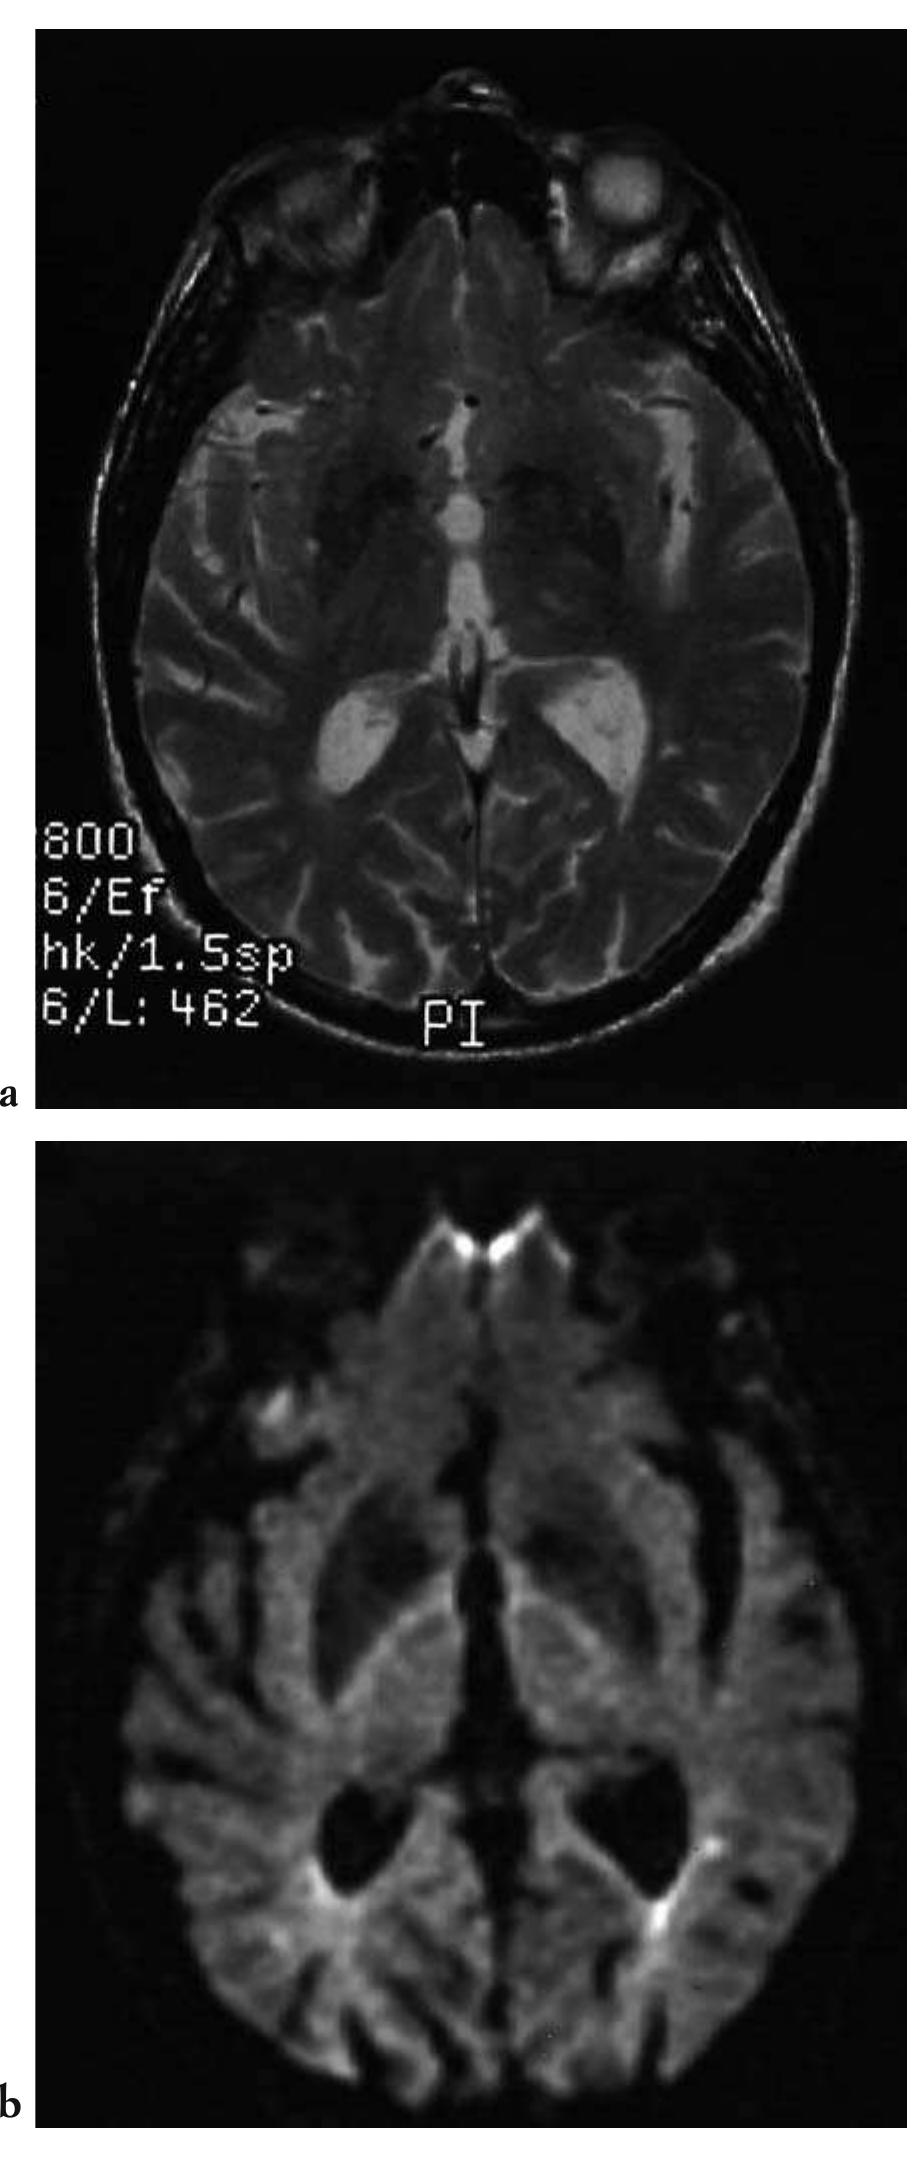

![Fig. 2.27 - Multiple contusive and lacerative haemorrhagic cere- bral foci in the acute phase. The T2-weighted sequence (a) shows multiple areas of signal hyperintensity within which haemor- rhagic components cannot be distinguished. The long scan time often results in motion artefacts. The echo-planar sequence (b), which is more sensitive to T2*-weighted tissue, enables the iden- tification of areas of hypointense signal caused by the presence of subacute haemorrhage (deoxyhaemoglobin). Motion artefacts can also be reduced by obtaining the acquisition in approxi- mately 500 msec. [a) T2-weighted MRI; T2*-weighted MRI].](https://figures.academia-assets.com/35610716/figure_169.jpg)